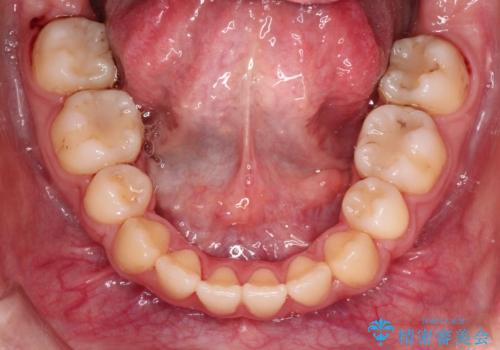

歯を抜いてスペースを作ることで、前歯を下げることができました。

ハーフリンガルということで治療期間が3年近くかかりましたが、口元もしっかり下がり満足していただきました。